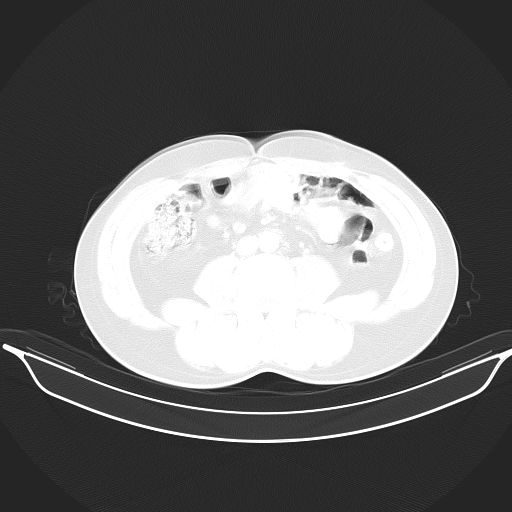

标题: CT25490:男,40岁,体检发现;无其它不适。 [打印本页]

标题: CT25490:男,40岁,体检发现;无其它不适。

考虑右下肺周围性肺癌并肺内多发转移,纵隔淋巴结转移!

支持 !考虑右下肺周围性肺癌并肺内多发转移,纵隔淋巴结转移,(气管前腔静脉后,隆突下,主动脉弓下都有了)

1、均为转移,原发灶不在肺内。2、肺癌肺转移。